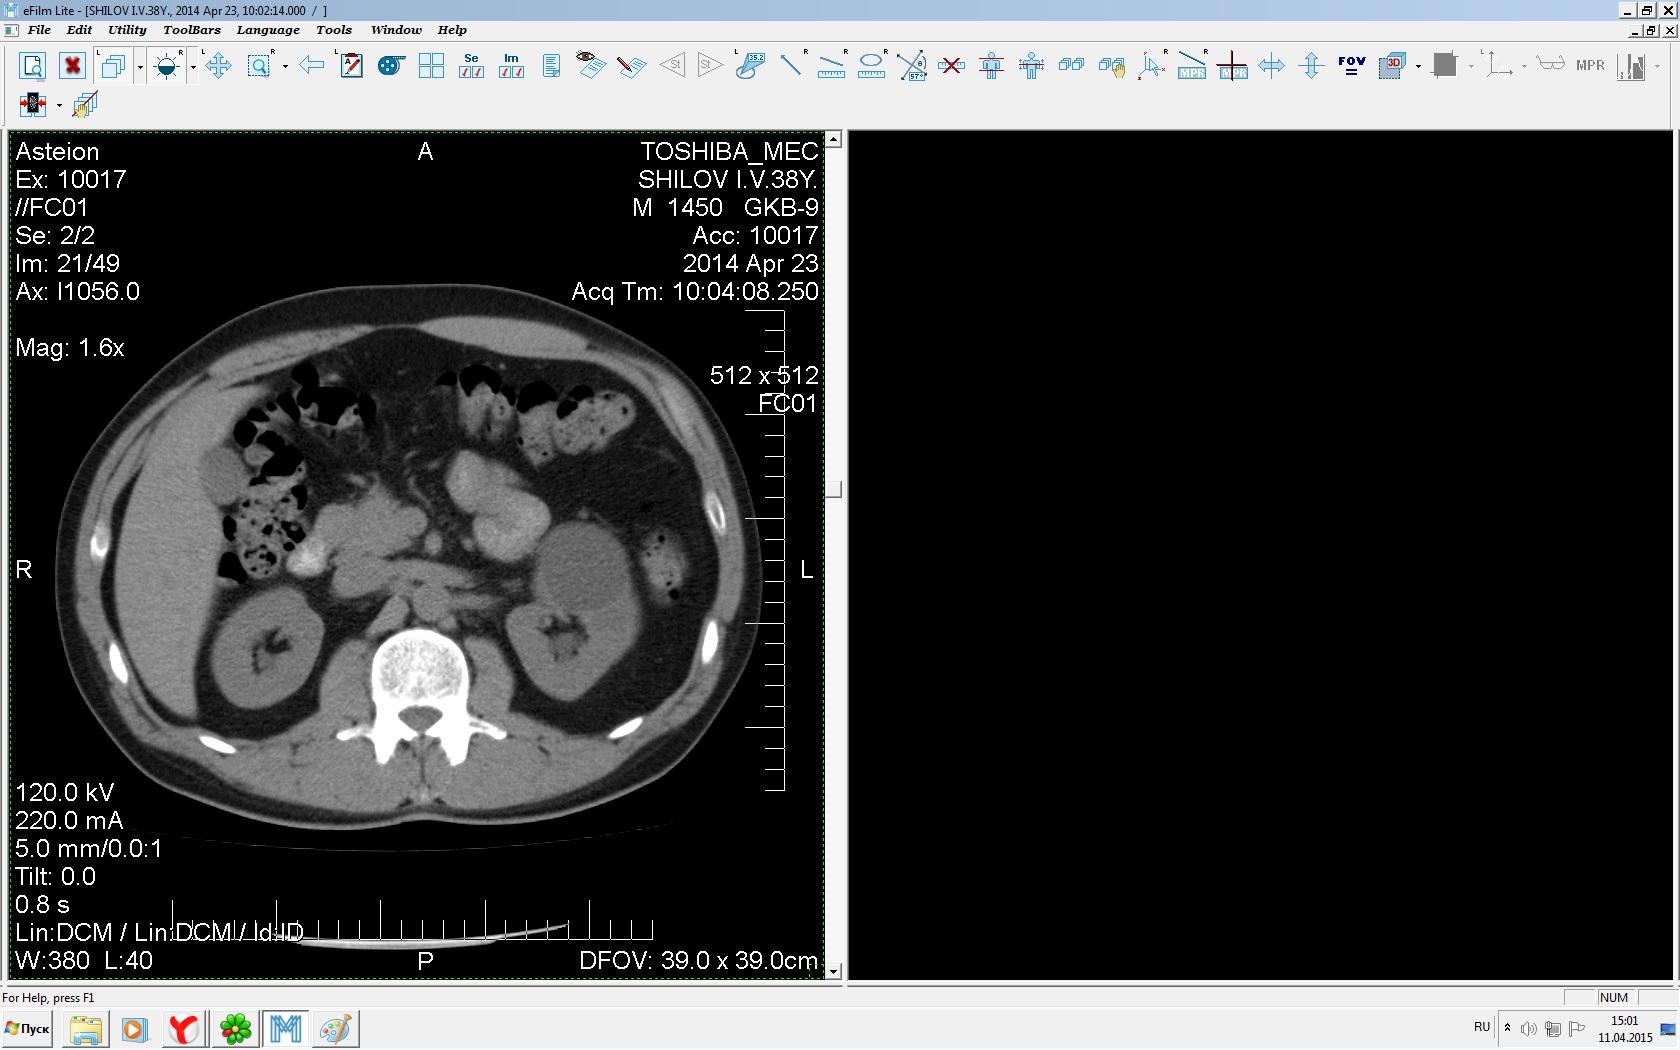

Здравствуйте. У меня киста левой почки. Из заключения: левая почка увеличена, деформирована за счёт наличия в среднем сегменте округлого жидкостного +6, +15 HU образования 66х53 мм, деформирует, поддавливает чаше-лоханочную систему. Сосудистые ножки структурные. В урологии мне сперва предложили лапароскопию, когда я лёг на операцию - изменили на полостную в связи со сложностью. Потом сказали что шансов вырезать кисту без почки практически нет. Даже если кисту удалить чудесным способом, то почка всё равно сложится и не будет работать. В итоге операцию отменили. Скажите, пожалуйста, есть ли современный метод удалить кисту и сохранить почку в моём случае? Томография почки в приложениях. Заранее благодарю.

Эту кисту можно просто пропунктировать, аспирировать и склерозировать - под местной анестезией. Ничего сверхестетственного не определяется по данным КТ. Можете написать мне на почту. aristova-tatyana@mail.ru